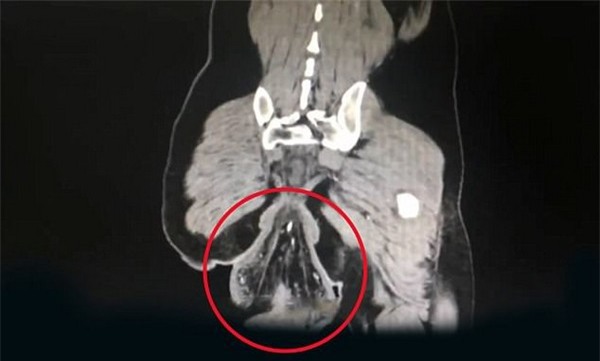

Người này lập tức được đưa vào bệnh viện, nơi các bác sĩ xác định khối u trồi ra từ hậu môn của anh ta là một phần trực tràng đã bị sa xuống và trồi ra ngoài do bị mất đi sự gắn kết trong cơ thể của bệnh nhân.

Các bác sĩ cho biết nguyên do của sự việc là vì bệnh nhân đã ngồi trong bồn cầu quá lâu, ít nhất trong 30 phút, khiến phần trực tràng bị sa xuống qua lỗ hậu môn. Bệnh nhân cũng cho biết anh có thói quen vừa dùng smartphone vừa đi vệ sinh và trước khi sự việc xảy ra, anh đã chơi game trong lúc đi đại tiện và thời gian ngồi trong nhà vệ sinh cũng dài hơn 30 phút.

Theo bác sĩ Su Dan, người điều trị cho bệnh nhân thì anh này đã bị tổn thương trực tràng và tình trạng là rất nghiêm trọng.

Các bác sĩ sau đó đã tiến hành phẫu thuật để cắt bỏ phần trực tràng bị trồi ra ngoài. Hiện bệnh nhân đang trong quá trình hồi phục.